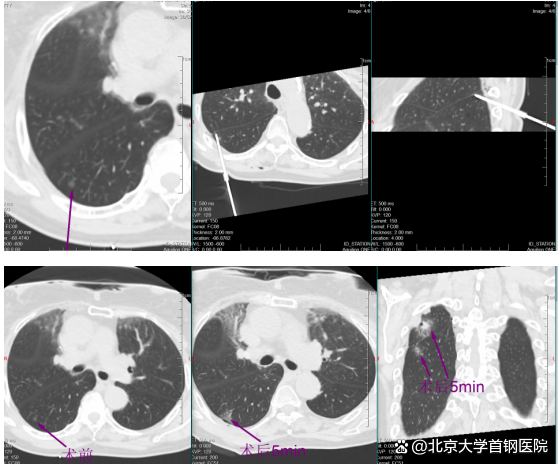

image

稍后,于明川与冯文汉等团队成员密切配合,向难度更高的第二枚结节发起冲击。这枚结节藏在叶间裂与胸膜构成的狭小夹角内,可操作空间极小,如同在“夹缝中绣花”。按照术前预案,于明川放弃平行进针思路,采用由下而上的特殊进针方式,巧妙避开关键解剖结构。针尖精准抵达结节区域,经过反复测量确认安全后,30瓦功率持续消融一分钟。术中,黄女士的心率、血压始终平稳,未出现任何不良反应。术后CT扫描证实,结节被完全覆盖,烧灼区与叶间裂仅隔几毫米,这毫厘之间的精准,正是生命安全的坚实屏障。